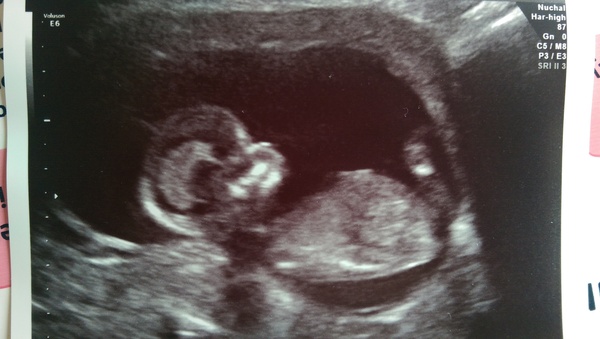

Hi All, difficult catching up! Was tied up with M day and my birthday and scan yesterday! Was great seeing baby and fingers crossed results come back positive.

jessica congratulations on your scan :)

Thanks shoot it is so amazing to see baby. Keep having to remind myself it's still in there when I leave the hospital!